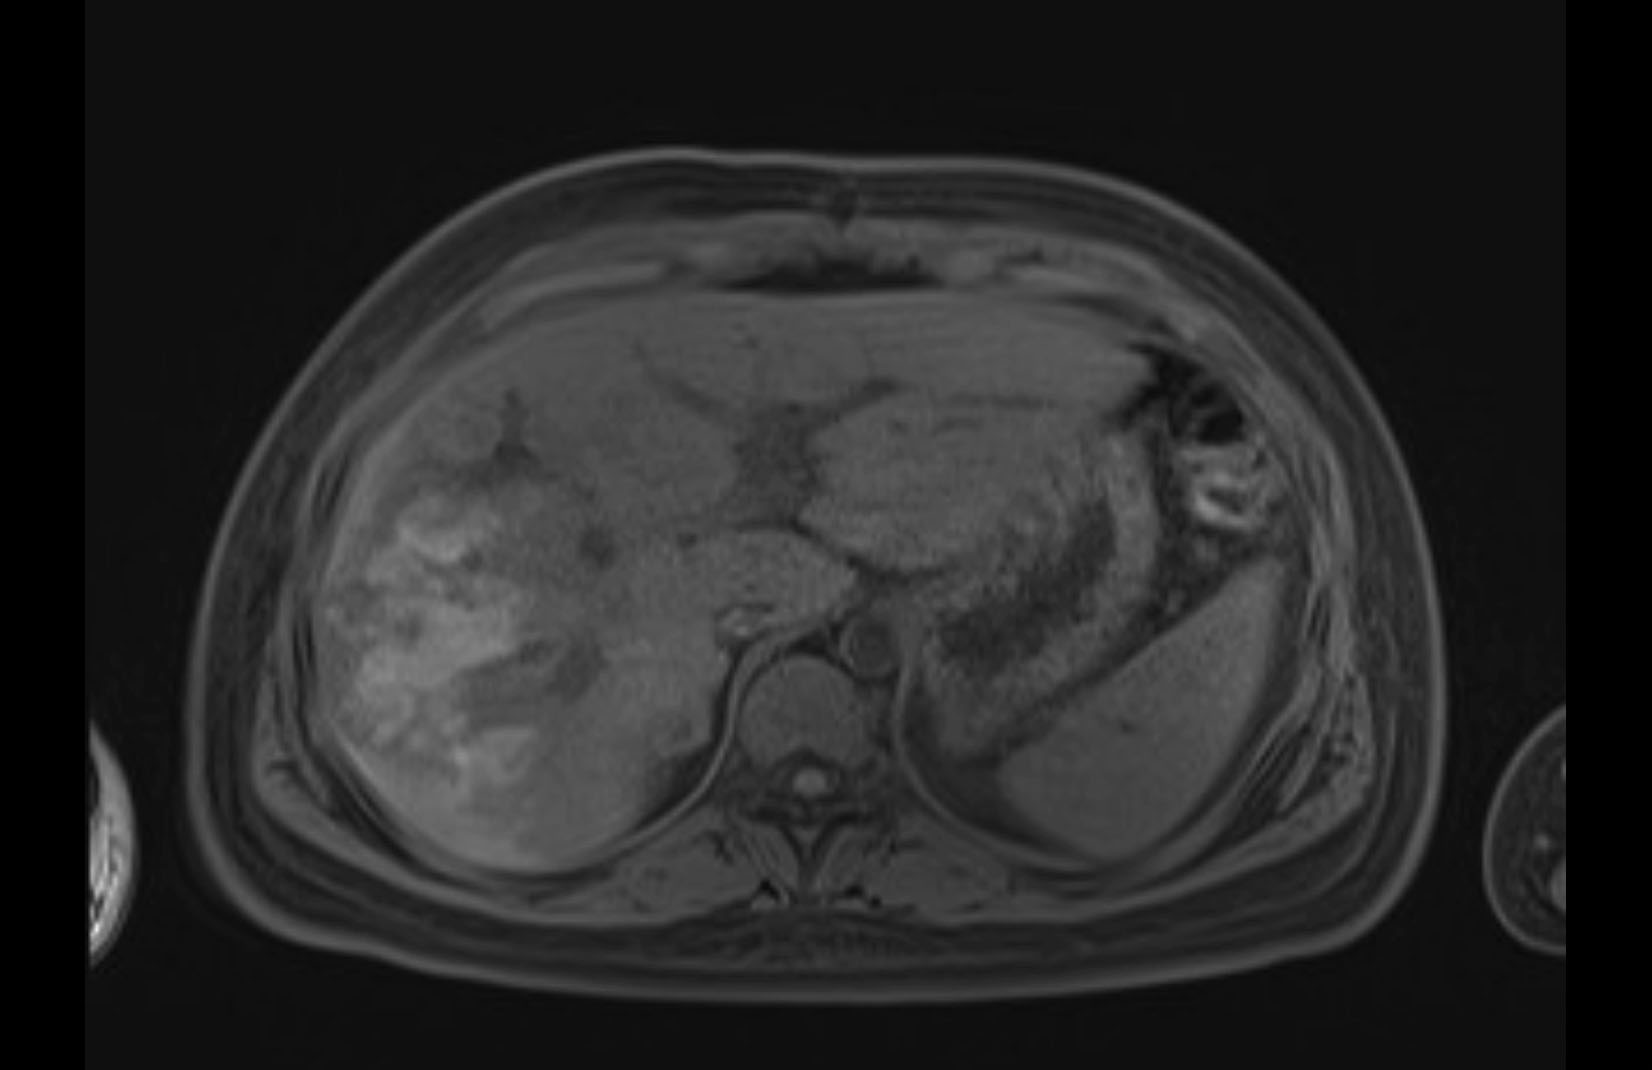

MRI T1

Imaging analysis

Based on initial findings, which issue(s) would you be most concerned about?